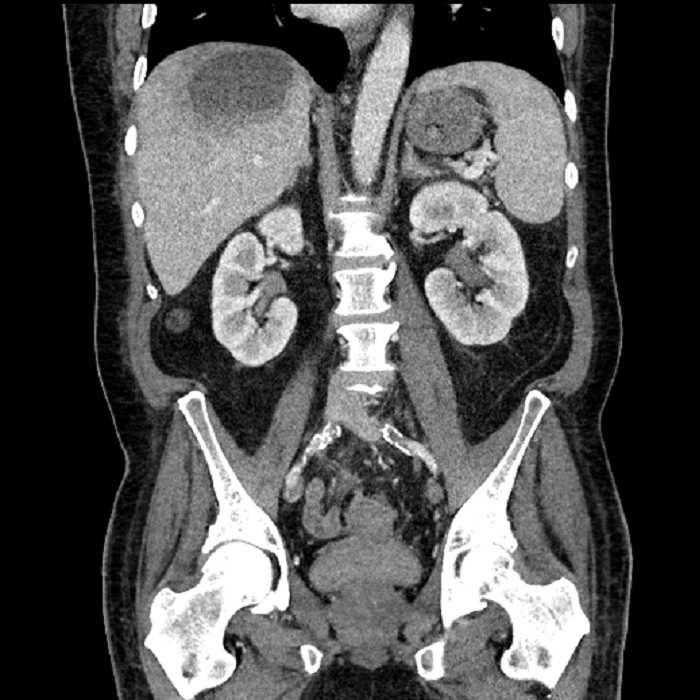

Age: 63

Sex: Male

Indication: Abdominal pain

• Large fluid density structure in hepatic segments 7 and 8 measuring 10 x 7 x 7 cm with internal septation and circumferential ill-defined low density compatible with edema

• Peripherally enhancing subcapsular collections along the anterior margin of the left hepatic lobe measuring 3 x 1 cm and 2 x 1 cm

• Clearly marginated fluid density structure in segment 7 and several other scattered tiny hypodensities, which likely represent cysts

Acute sigmoid diverticulitis complicated by a small contained perforation and a large abscess in the right hepatic lobe. Additional small subcapsular abscesses along the anterior margin of the left hepatic lobe.

• The classic CT imaging appearance is a double target sign with internal low density surrounded by an internal enhancing rim (capsule) and a low density external rim (edema)

Hepatic abscess showing the double target sign with low density internally surrounded by a thin inner enhancing rim (red arrow) and ill-defined outer low density rim (yellow arrow). Blue arrow indicates an internal septation. Red arrows: additional smaller subcapsular abscesses. Red arrow: focal contained perforation associated with diverticulitis.